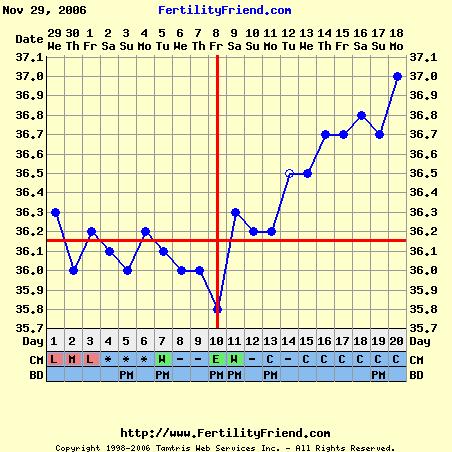

Éva, ez aztán a szép görbe! Igaz, én kicsi meglepődtem, hogy a 10. napon volt a pé-ed, de mivel nem esik vissza, tényleg akkor lehetett. Akkor viszont nemsokára tesztelhetsz!